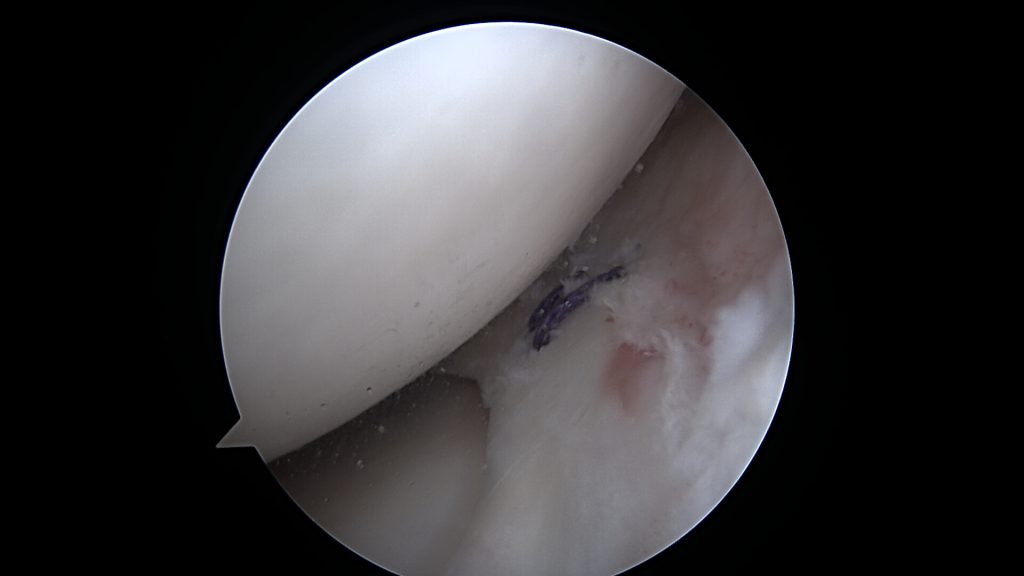

Potwierdzenie rozpoznania tego uszkodzenia następuje podczas zabiegu bardzo szybko. Zaraz po wprowadzeniu optyki do stawu po prostu widzimy łąkotkę nie tam gdzie powinna być, czyli tuż przed kamerą. Po wykonaniu inspekcji wszystkich dostępnych części stawu dokonuje się odświeżenia miejsca uszkodzenia oraz „repozycji” uszkodzonego fragmentu łąkotki (przepchnięcia jej na swoje miejsce). Następnie przy pomocy szwów zakładanych artroskopowo mocują się ją na swoim miejscu.

W tym przypadku jej proste przyszycie nie będzie możliwe, nie będzie po prostu stabilnych fragmentów łąkotki które można złapać szwem. Konieczne jest zastosowanie techniki „biokanapki”. Zabieg polega na owinięciu błoną kolagenową uszkodzonego fragmentu łąkotki, błona pełni tu rolę worka trzymającego włókna łąkotki razem. Szwy zakłada się poprzez błonę kolagenową stabilizując tym samym luźne uszkodzone fragmenty łąkotki. Na koniec zabiegu podaje się komórki macierzyste do środka stworzonej w ten sposób przestrzeni. Postępowanie pozabiegowe jest w tym przypadku określone odpowiednim protokołem rehabilitacyjnym.